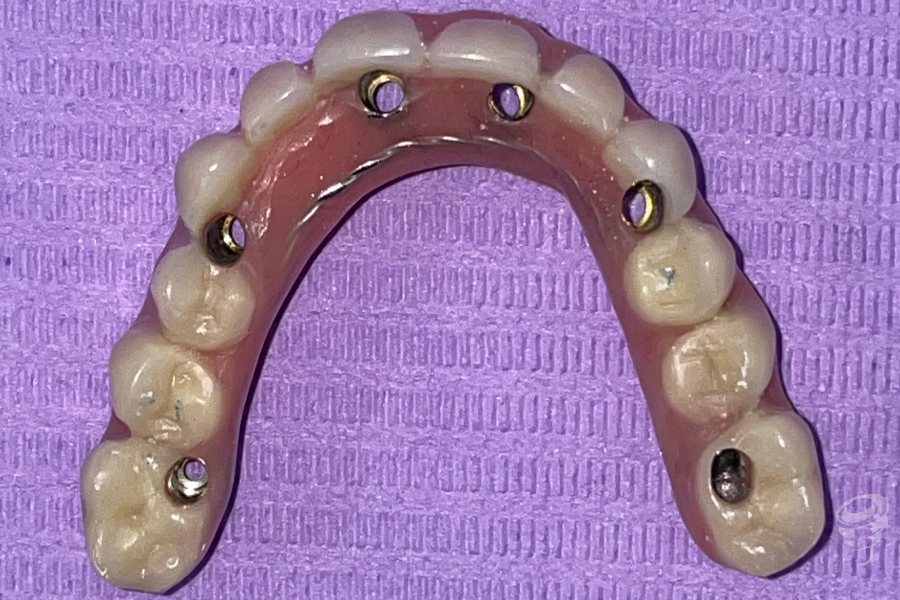

Orto postoperatorio inmediato + Carga inmediata. (Imagen 10 y 11)

Imagen 12

Imagen 13

Orto a los 3 años de evolución + Prótesis definitiva. (Imagen 12 y 13)